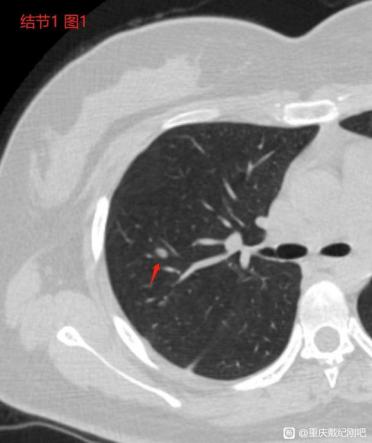

这是2021.1在新桥医院拍的CT及报告: